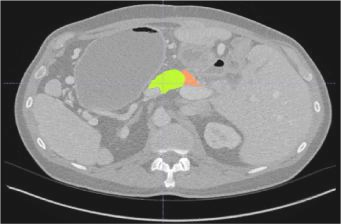

Creating large-scale and well-annotated datasets to train AI algorithms is crucial for automated tumor detection and localization. However, with limited resources, it is challenging to determine the best type of annotations when annotating massive amounts of unlabeled data. To address this issue, we focus on polyps in colonoscopy videos and pancreatic tumors in abdominal CT scans; both applications require significant effort and time for pixel-wise annotation due to the high dimensional nature of the data, involving either temporary or spatial dimensions. In this paper, we develop a new annotation strategy, termed Drag&Drop, which simplifies the annotation process to drag and drop. This annotation strategy is more efficient, particularly for temporal and volumetric imaging, than other types of weak annotations, such as per-pixel, bounding boxes, scribbles, ellipses, and points. Furthermore, to exploit our Drag&Drop annotations, we develop a novel weakly supervised learning method based on the watershed algorithm. Experimental results show that our method achieves better detection and localization performance than alternative weak annotations and, more importantly, achieves similar performance to that trained on detailed per-pixel annotations. Interestingly, we find that, with limited resources, allocating weak annotations from a diverse patient population can foster models more robust to unseen images than allocating per-pixel annotations for a small set of images. In summary, this research proposes an efficient annotation strategy for tumor detection and localization that is less accurate than per-pixel annotations but useful for creating large-scale datasets for screening tumors in various medical modalities.